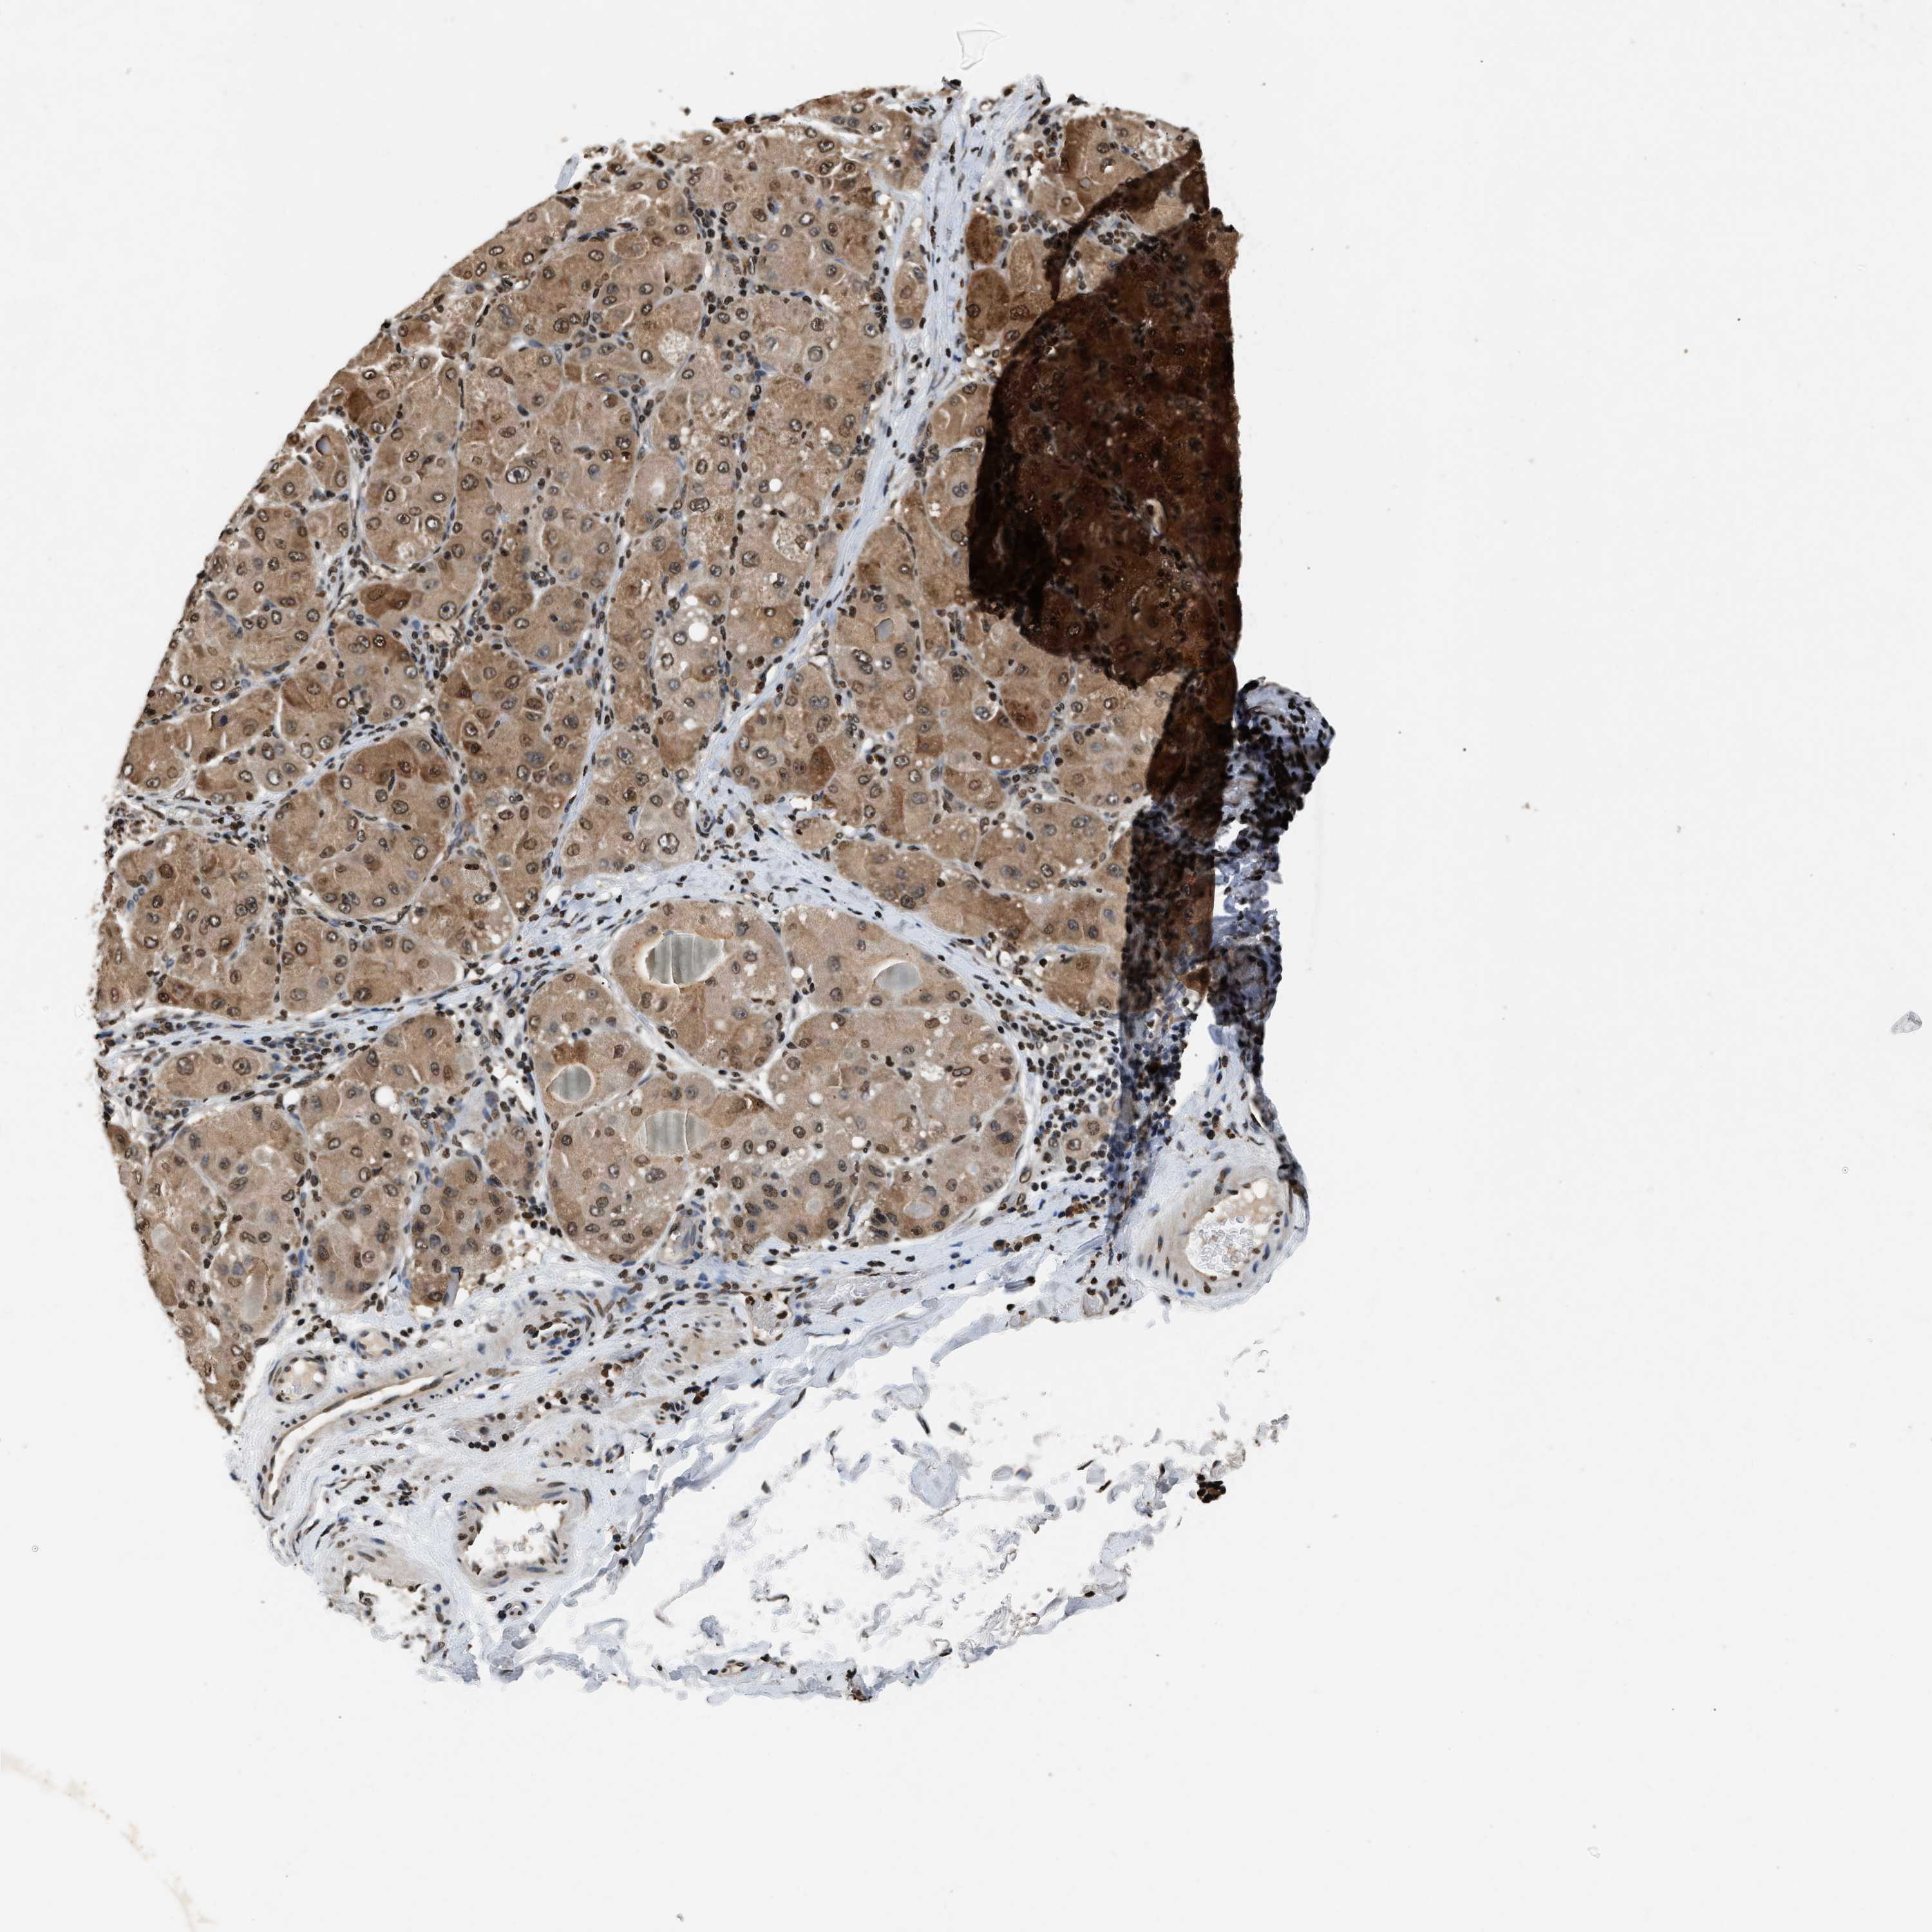

LIVER CANCER - Protein expressioni

A mouse-over function shows sample information and annotation data. Click on an image to view it in a full screen mode. Samples can be filtered based on level of antibody staining by selecting one or several of the following categories: high, medium, low and not detected. The assay and annotation is described here.

Note that samples used for immunohistochemistry by the Human Protein Atlas do not correspond to samples in the TCGA dataset.

Antibody stainingi

Antibody staining in the annotated cell types in the current human tissue is reported as not detected, low, medium, or high, based on conventional immunohistochemistry profiling in selected tissues. This score is based on the combination of the staining intensity and fraction of stained cells.

Each image is clickable and will lead to virtual microscopy that enables deeper exploration of all samples and also displays staining intensity scores, fraction scores and subcellular localization as well as patient and tissue information for each sample.

Antibody HPA019955

Staining

High

Medium

Low

Not detected

Intensity

Strong

Moderate

Weak

Negative

Quantity

>75%

75%-25%

<25%

None

Location

Nuclear

Cytoplasmic/membranous

Cytoplasmic/membranous,nuclear

Cholangiocarcinoma

Carcinoma, Hepatocellular, NOS